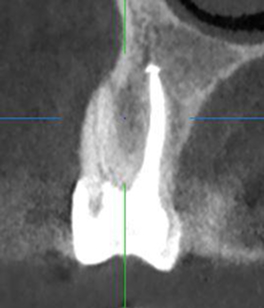

Лечение: Проведено перелечивание корневых каналов под микроскопом с удалением ранее внесённых материалов, тщательной механической и медикаментозной обработкой каналов и их последующей герметичной обтурацией. После лечения каналов выполнено восстановление коронковой части зуба.

После завершения эндодонтического лечения и стабилизации состояния зуба врач-ортопед провёл подготовку зуба под протезирование. Изготовлена и зафиксирована коронка. (Фото 2 и 3).

Результат: Болевые ощущения при накусывании полностью устранены, дискомфорт при жевании отсутствует. Зуб сохранён и полноценно восстановлен. После установки керамической коронки восстановлены анатомическая форма и жевательная функция.